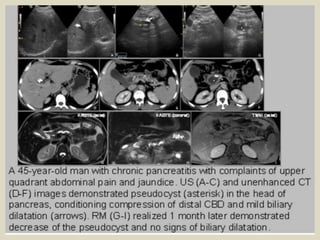

Hydatid cyst ruptured into the biliary tract A 45 years old female, with a history of cholecystectomy 10

years ago, presented with abdominal pain. (a) Abdominal US revealed a multivesicular hydatid cyst of

the liver dome (Gharbi type III). (b) Communication of the hydatid cyst with the right bile duct, and

presence of a hydatid material in the bile duct. (c,d) CT shows the dilated bile ducts, the communication

of the cyst with the right bile duct, and the presence of hydatid material into the biliary tract. (e)

Intraoperative cholangiography showed the presence of hydatid vesicles in the lower bile duct.